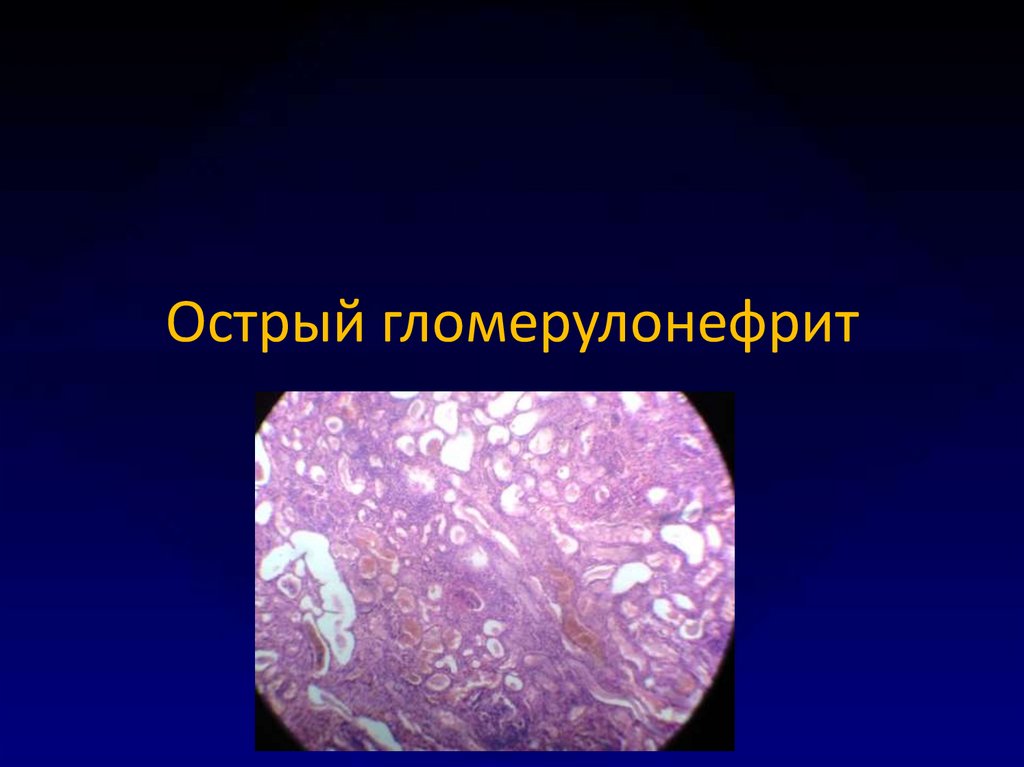

Механизм остро го диффузного гломерулонефрита